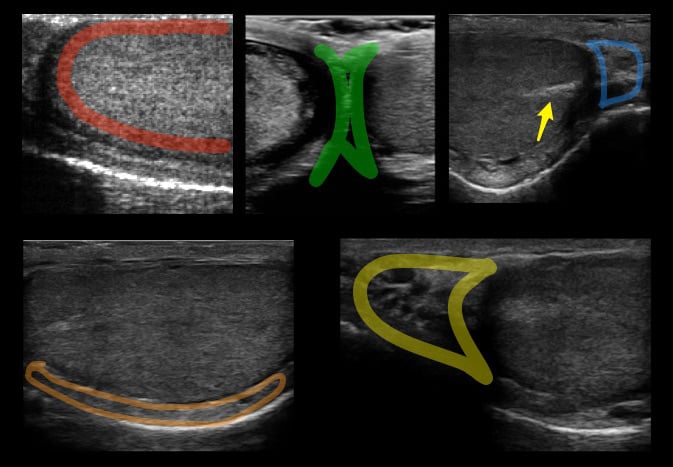

- The normal testis has midgray or medium-level echoes and is homogeneous in appearance. (Figure 3)

Figure 3. Red: Image of the normal testicle with homogenous echotexture. Green: Median raphe. Blue: Tail of the epididymis. Orange: Body of the epididymis. Yellow: Head of the epididymis. Arrow: Mediastinum testis seen as a linear echogenic band

- The epididymis has similar or slightly increased echogenicity as compared to the normal testis.

- The mediastinum testis is seen as a linear echogenic band running parallel to the epididymis, best seen on sagittal view.

- The appendix testis and appendix epididymis are small ovoid hyperechoic protuberances found at the superior pole of the testis, normally hidden by the epididymal head. Unless outlined by fluid from a hydrocele, they are difficult to find on ultrasound.